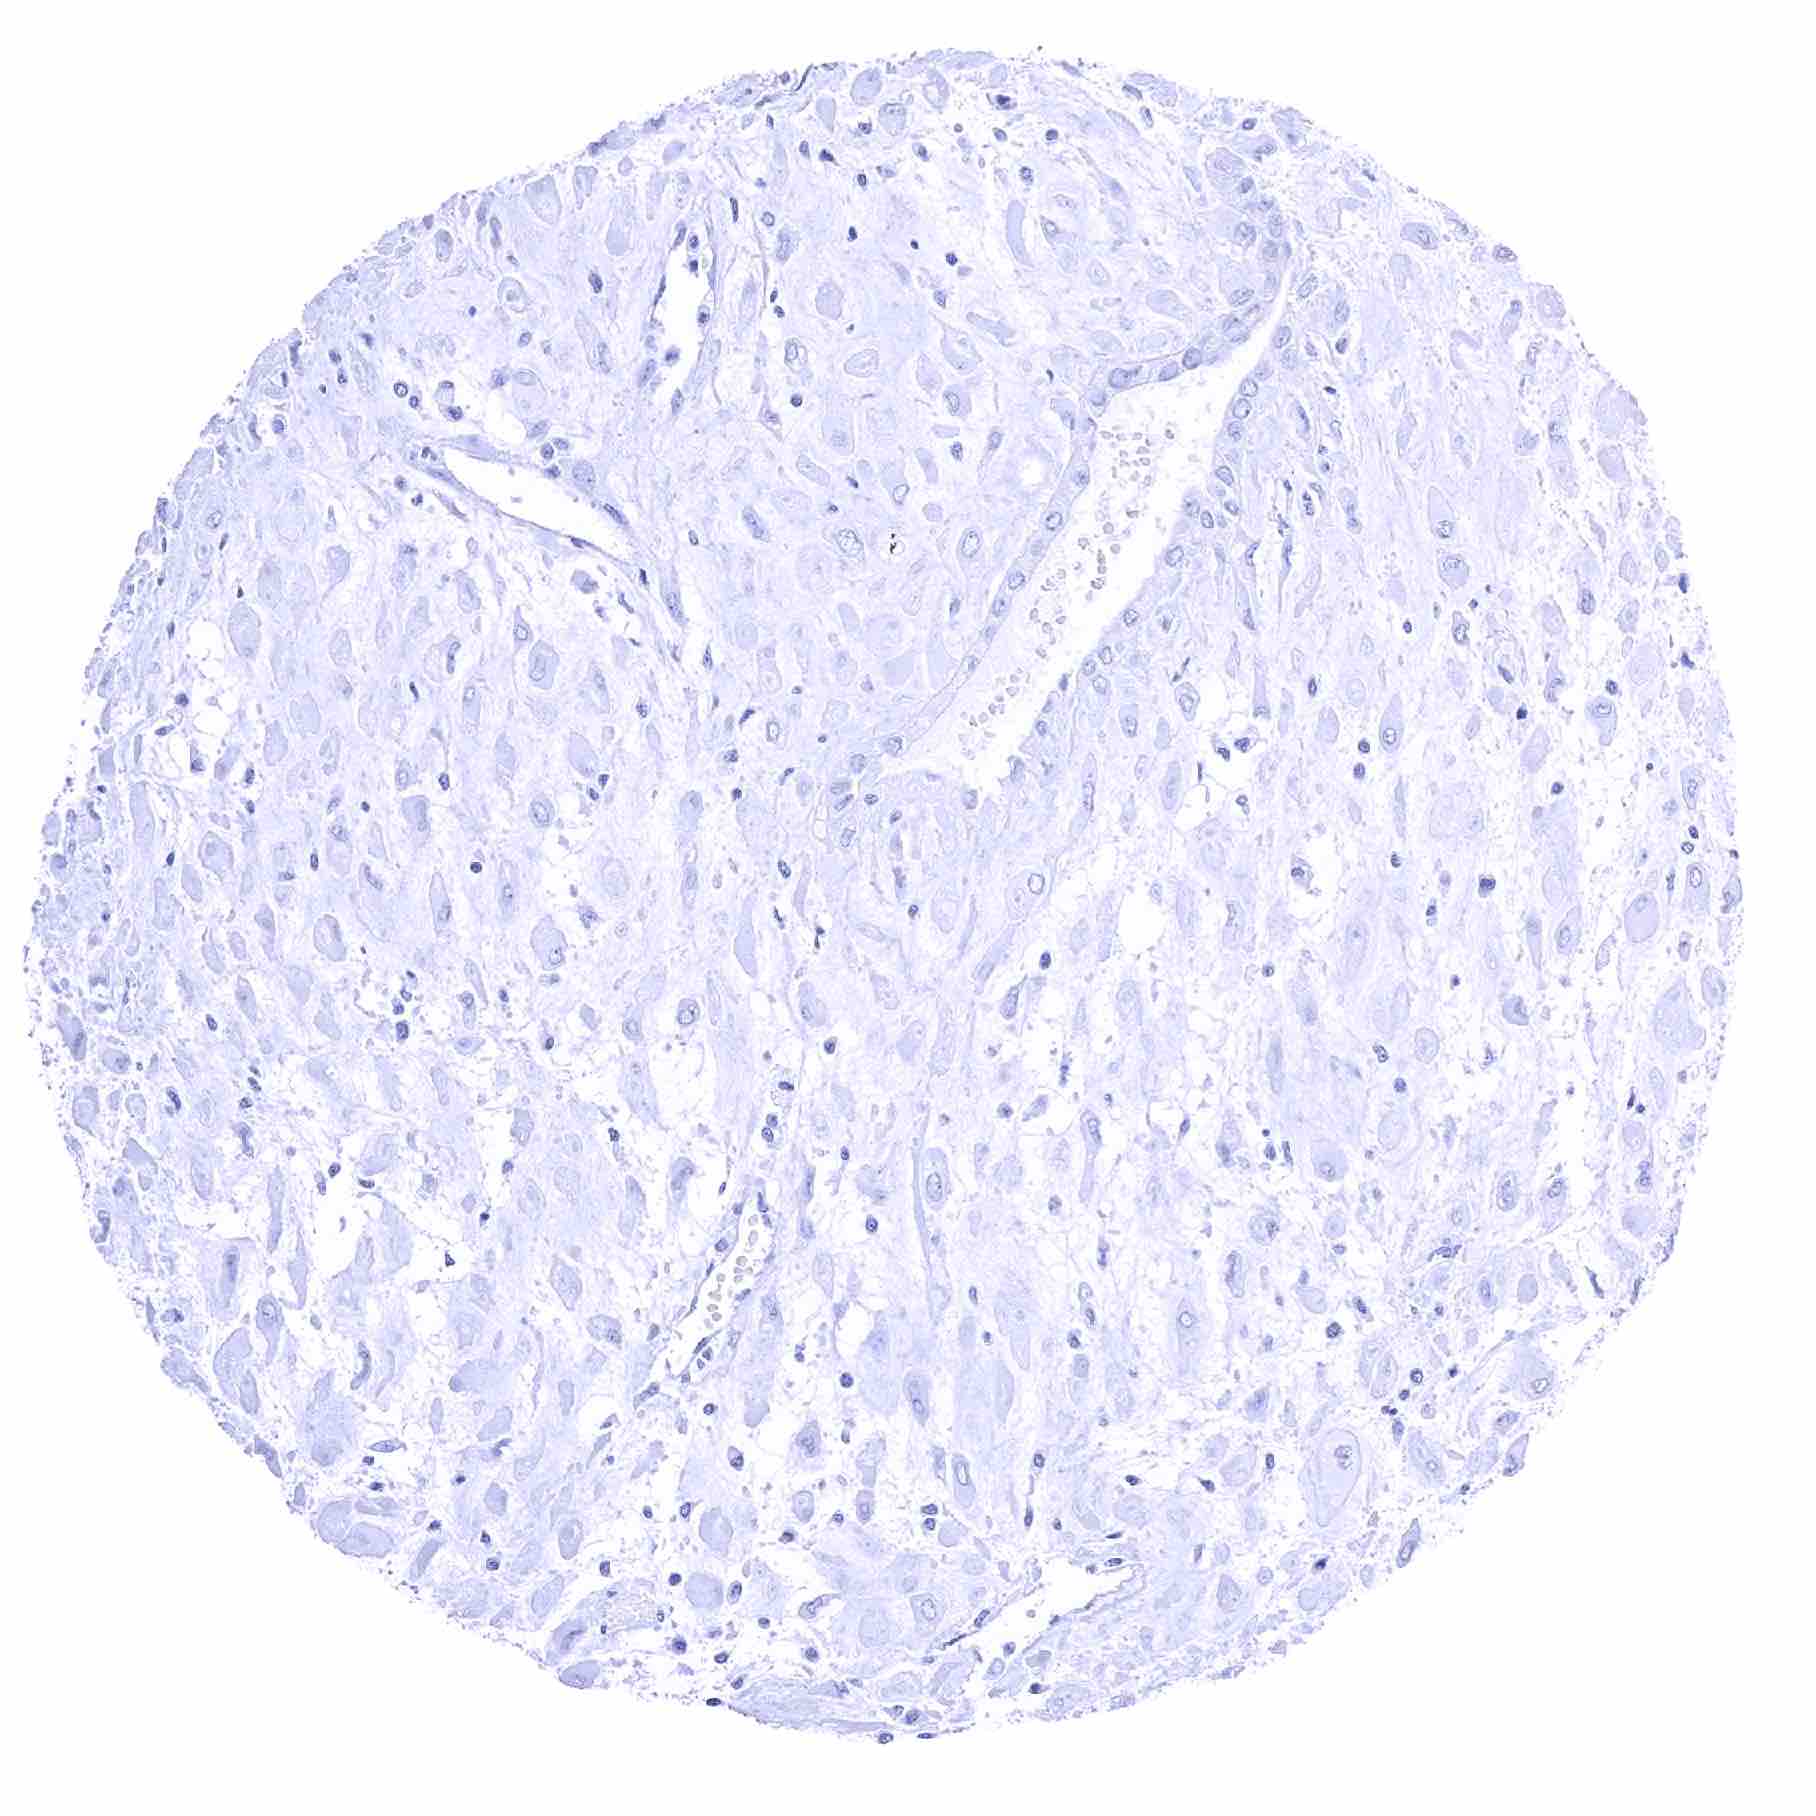

Uterus, ectocervix